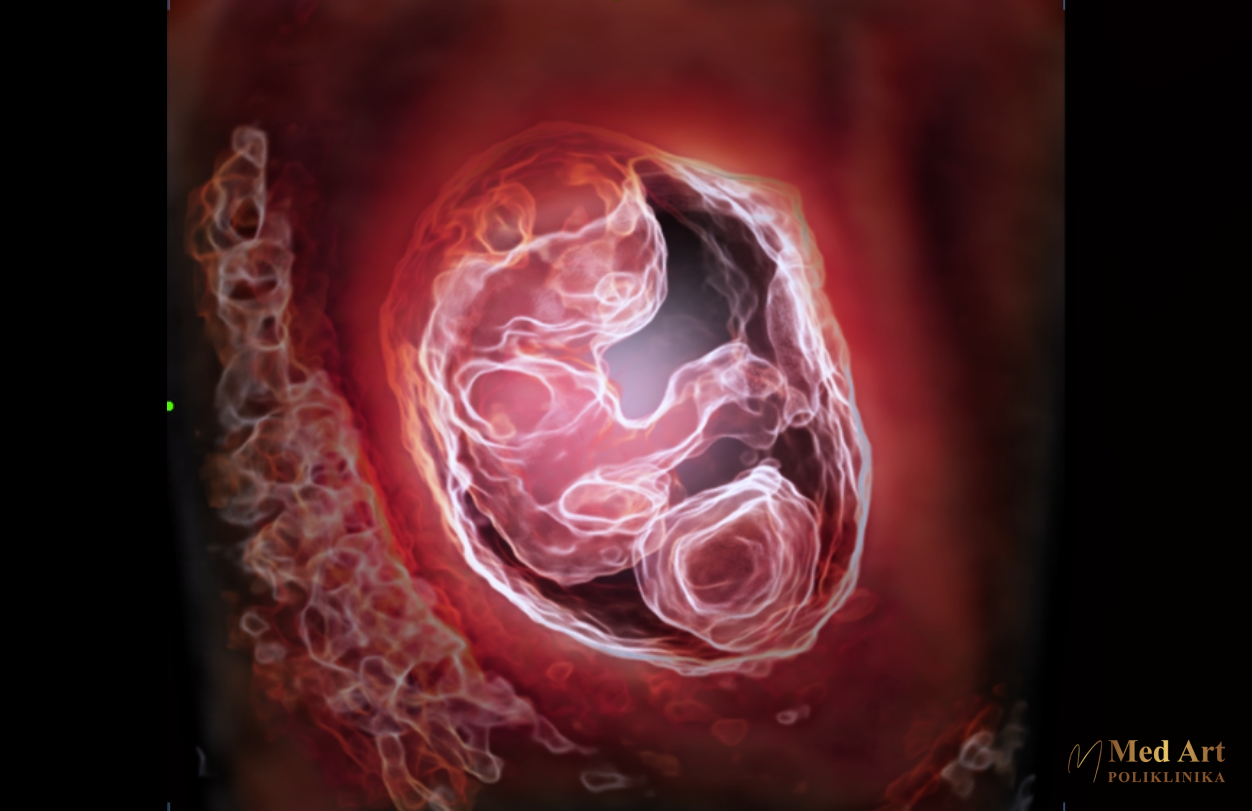

U galeriji koja slijedi, možete vidjeti ultrazvučne slike beba u 6., 7., 8., 12., 14., 20., 21., 24., 27. i 34. tjednu trudnoće, koje prikazuju njihov razvoj od rane trudnoće pa sve do priprema za dolazak na svijet.